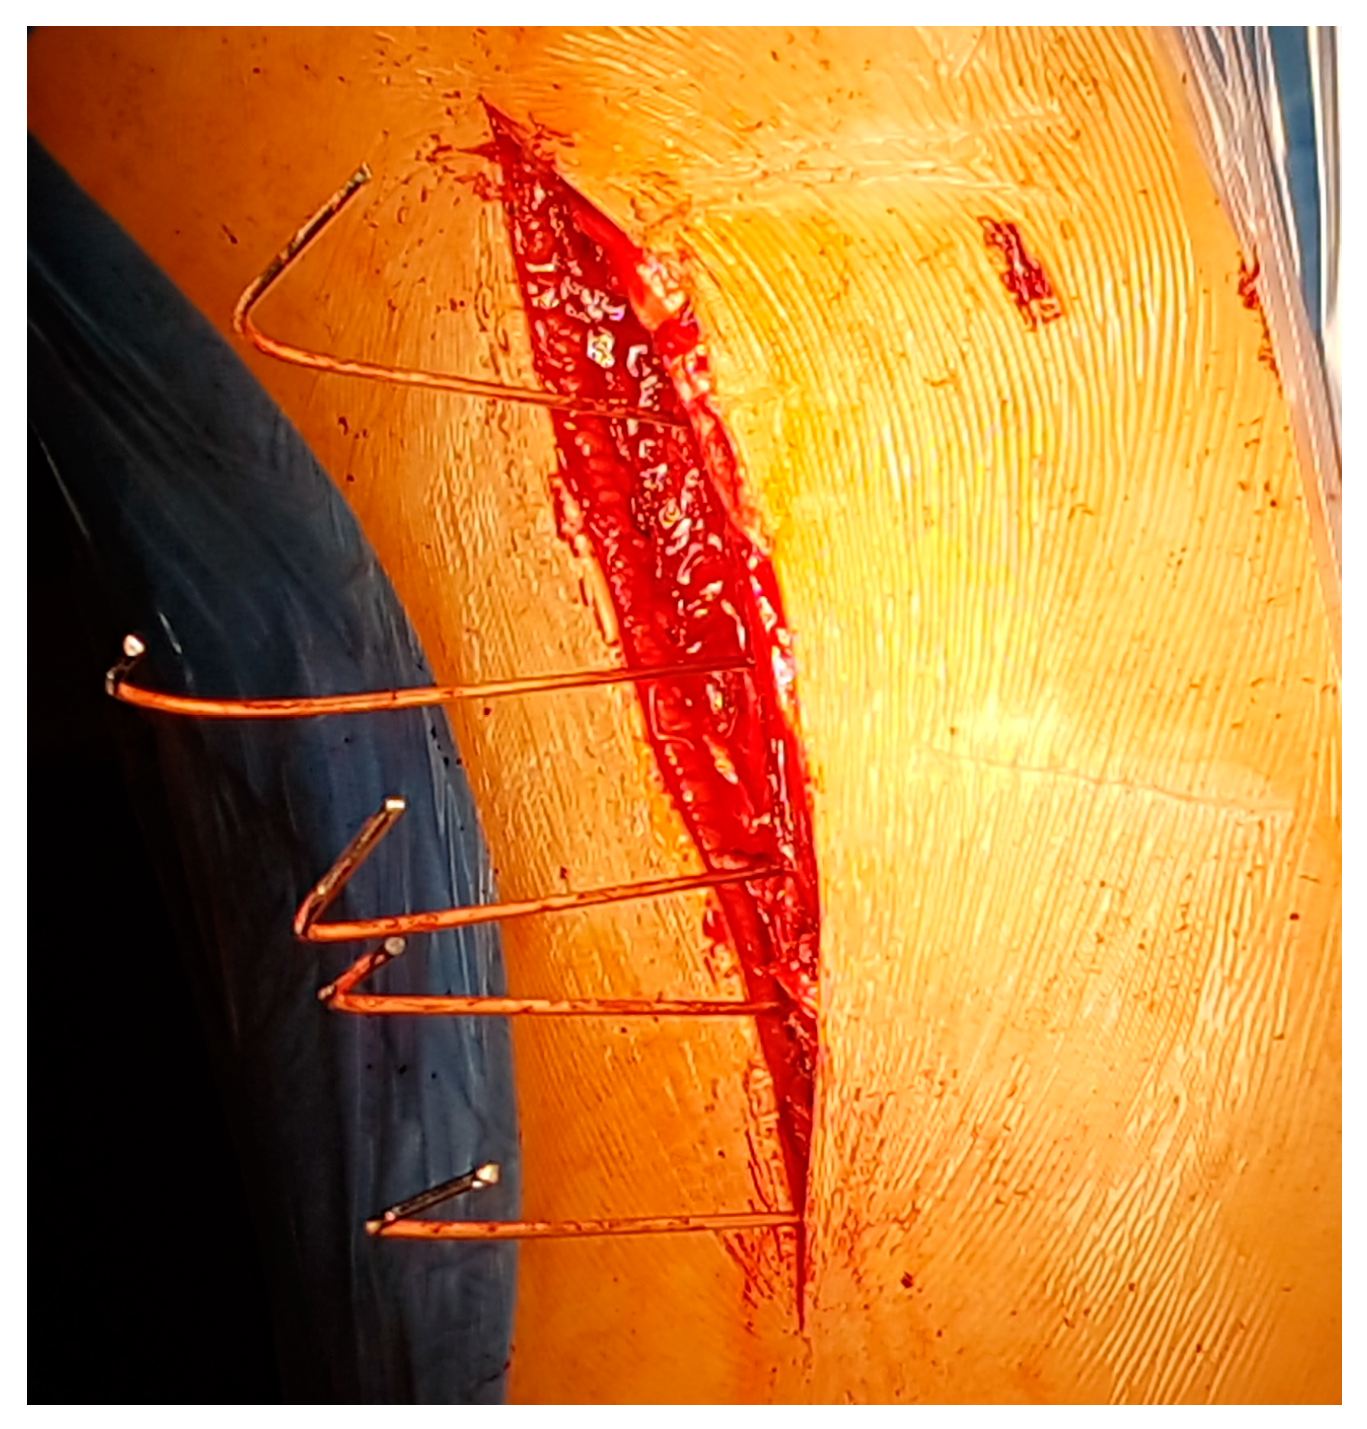

A Wiltse approach is used [13,14,15]. A midline skin incision is made, and the superficial and deep fasciae are opened longitudinally, approximately 2–3 cm laterally on the convex side. A blunt separation of the medial multifudus and the lateral longissimus is made with the fingers (Figure 1 and Figure 2).

View of the space between the lateral longissimus and medial multifidus muscles.

This makes it possible to identify the transverse process and joint of each vertebra. K wire is stuck to the theoretical entry point of the screws at each level under fluoroscopy (Figure 3 and Figure 4); note they are bent at 90° to better identify their position on the X-ray.

View of the pins: they are stuck to the theoretical entry point and bent for a better identification on the X-ray.